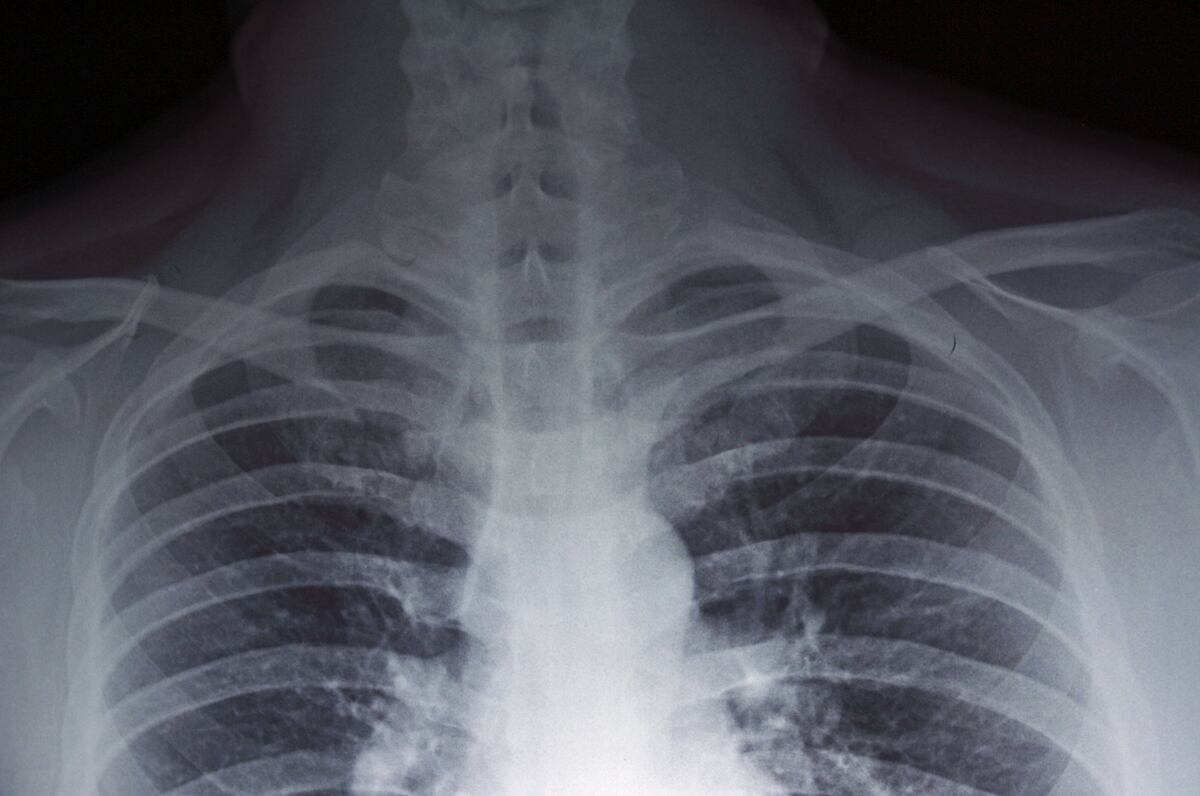

En cuanto a los síntomas característicos de la enfermedad, existen similitudes con respecto a la neumonía, por lo cual encendió las alertas y escaló la preocupación en el país: fiebre, dolores musculares y abdominales, así como dificultad respiratoria.